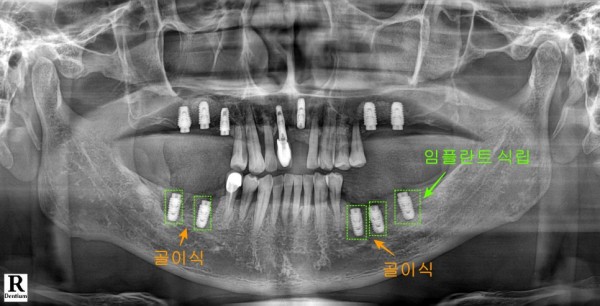

두 번째 치료 단계에서는 아래쪽 어금니 부분에 집중했습니다.

첫 번째 치료에서 발치했던 부위들과 추가로

한 개의 어금니 부위에 총 다섯 개의 임플란트를 식립했습니다.

그런데 이 부위는 예상했던 것보다 뼈 손실이 훨씬 심각한 상태였습니다.